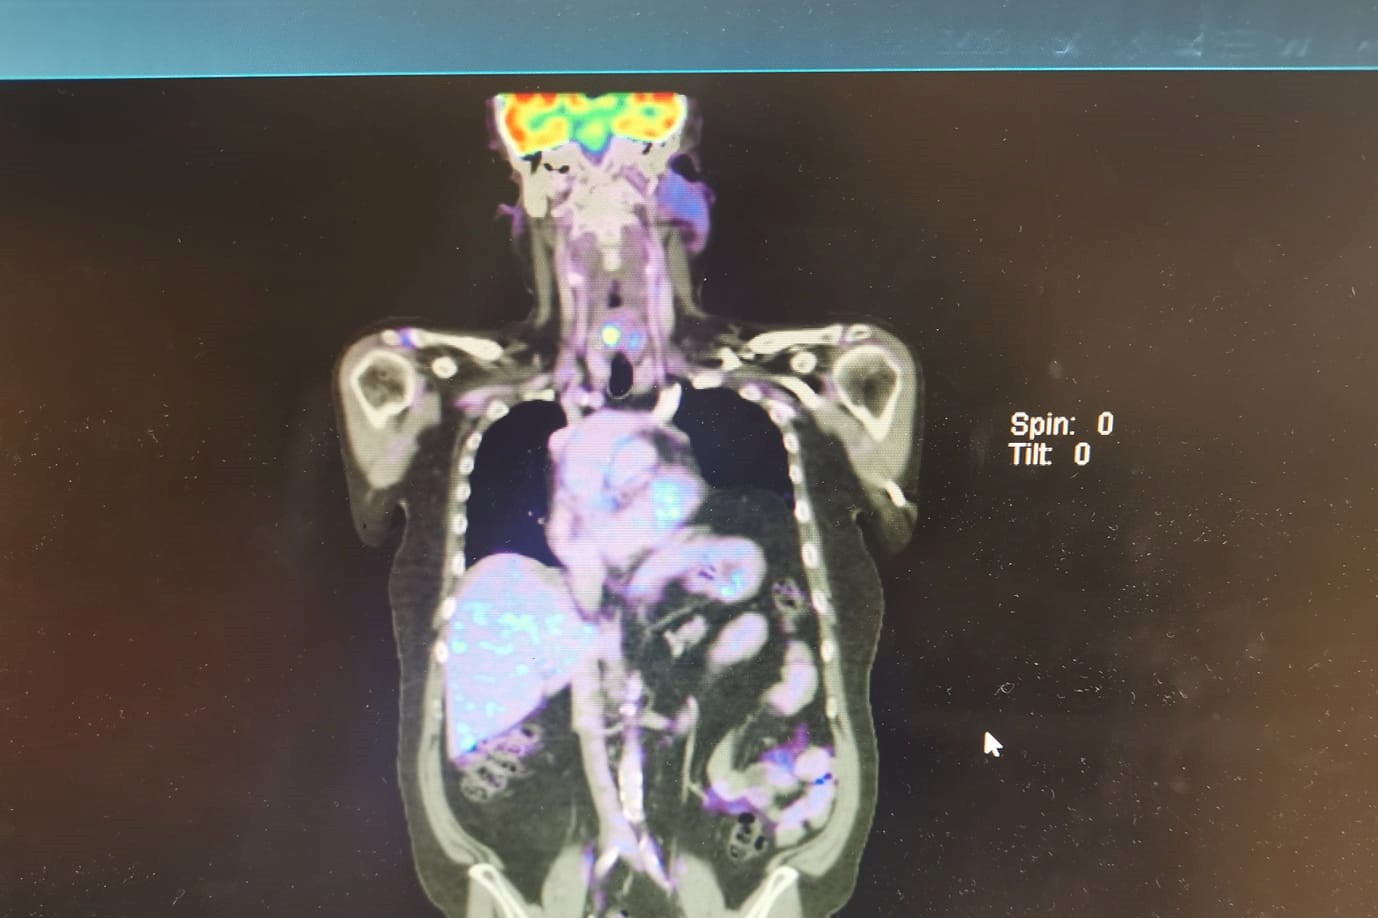

I was expecting to write this story with the title something like. “Well that’s not good news” or “Trial fails to meet expectations.” However, in a major unexpected twist it didn’t turn out like that at all. Call me paranoid or delusional but I had convinced myself that after what appeared to be initial successContinue reading “Riding The Emotional Rollercoaster”